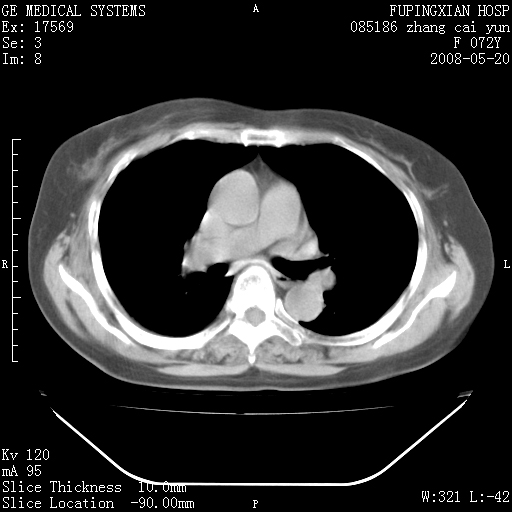

标题: CT13542:发热,咳嗽数日,经抗菌素治疗好转,请大家看排除 [打印本页]

标题: CT13542:发热,咳嗽数日,经抗菌素治疗好转,请大家看排除

有节段性阻塞性肺炎与不张,近段支气管狭窄,周围散在肿大淋巴结影,以周围型肺癌可能性大,建议纤支镜检查。

右肺上叶实变影,内见支气管充气征,右上叶支气管通畅,肺门区未见软组织密度影,抗炎治疗有效,考虑炎症,建议继续抗炎治疗复查。

右肺阻塞性肺炎  不除外支气管内膜结核

考虑为:右肺上叶感染性病变。建议:1)继续抗炎治疗后复查。2)必要时行纤支镜检查。

右上肺实变,间内有支气管充气征,考虑炎症,建议抗炎后复查